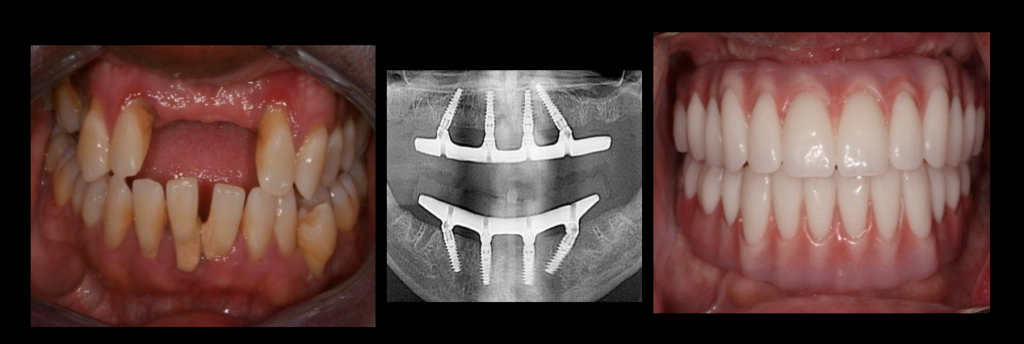

Can dental implants be done in 1 day?

The Teeth in One Day procedure is unique in that the provisional, fully functional teeth can be placed on the same day that the dental implants are received. See the article : Tooth Planting. These temporary teeth remain in place until the customized permanent teeth are ready to be placed.

How many implants are needed for full mouth?

Due to the softer bone in the upper jaw, the minimum amount of implants that can be placed for a full dentition is 4 implants, regardless of whether the final prosthesis is fixed or removable. You can’t do anything about 2-3 implants in the upper jaw or things are more likely to fail.